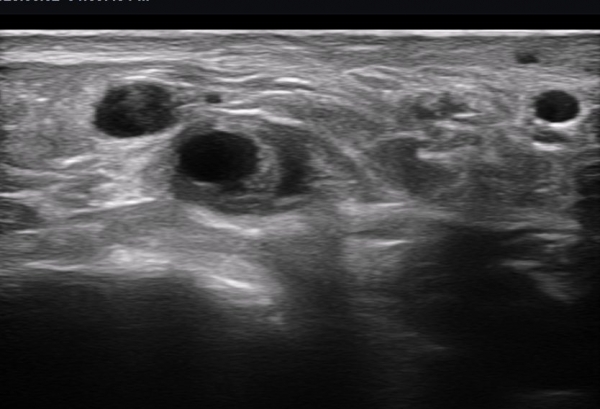

ÃÊÀ½ÆÄ ¼Ò°ß : ºñº¹½Å°æ Ⱦ´Ü¸é°Ë»ç¿¡¼­(»çÁø 1~13) ºñº¹½Å°æÀÇ Àú¿¡ÄÚ ºÎÁ¾°ú ´Üºñ°ñ°Ç³» ³¶Á¾¼º º´º¯ÀÌ °üÂûµÈ´Ù.